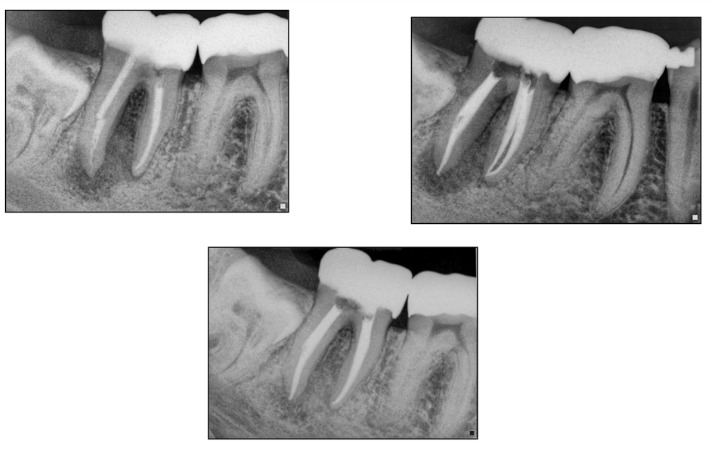

–periodontal disease (periodontitis) (figure 5)

Fig.5 This is a case that needed endodontic treatment, but also had the a separate issues of periodontal disease resulting in horizontal bone loss. I do not believe in this case one problem was contributory towards the other. He had generalized horizontal bone loss around all of his teeth. I performed the RCT and the lower right is a 6 month recall. The patient remains asymptomatic.

Finally there is the “gut feeling” of whether a tooth is savable or not. This is not scientific and it is variable. But I really feel it is worthy of discussion despite there being no real teaching method to a “gut feeling” approach. Anyone who has practiced (dentistry or medicine) for years will see conditions that are not necessarily discussed in a textbook. And over time we will learn how to deal with them better. This is developed over years of treating teeth and experiencing similar scenarios (figure 9). Admittedly though my gut feeling may sometimes be different than someone else. Even here in our office I might have some different interpretation of a case than my partners. But that is also one big advantage that I feel in working with my partners. In diagnostically challenging situations always talk about it together to gain another perspective that could prove very valuable. Everyday we share cases and gain perspectives from each other.

Fig.9 Here is a case done by Dr. Adam Monroe on 3/1/11. This tooth did have a deep probing near the apex on the distal root. Over the course of 3 appointments and using CaOH for 2 months the probing decreased to a normal 4mm and the 1.5 year recall shows excellent bone fill.